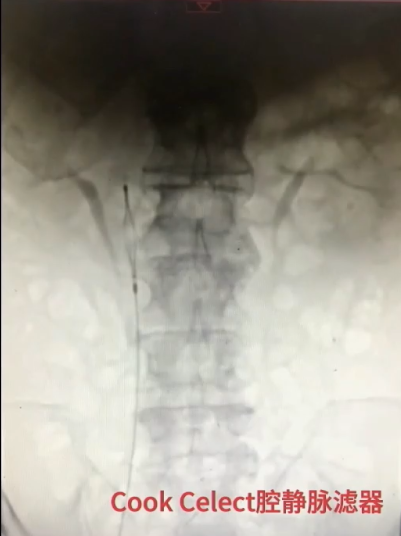

手术过程(一):局麻下,6F穿刺鞘穿刺右侧股静脉,造影见右肾静脉于第一腰椎下缘平面汇入腔静脉。换鞘后,引入腔静脉滤器,于第二腰椎上缘水平释放。